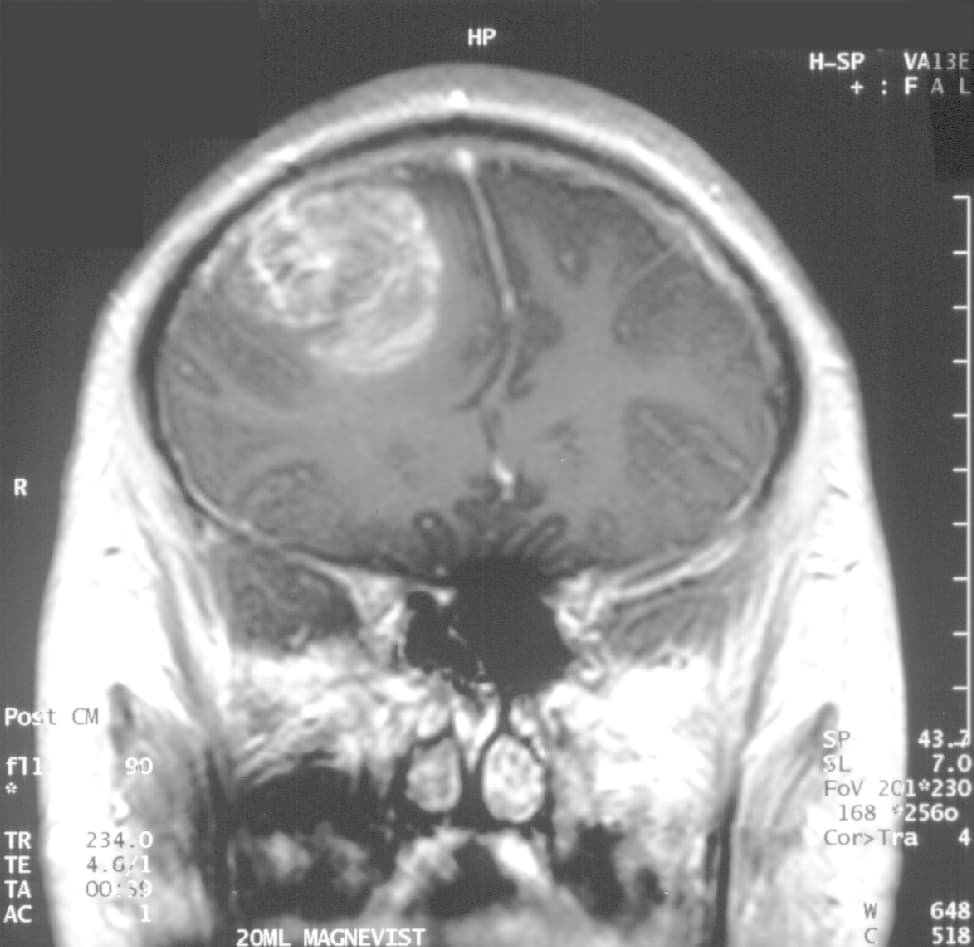

vignette | cérébrale avec injection de produit de contraste : Coupe frontale, glioblastome multiforme chez un enfant de 15 ans. vignette | cérébrale avec injection de produit de contraste, coupe sagittale, glioblastome multiforme chez un enfant de 15 ans. vignette | Aspect d'un glioblastome sur une lame d'histologie. Le (GBM) ou , également connu sous le nom d'« astrocytome de », est la tumeur primitive du cerveau la plus fréquente et la plus agressive. Le traitement peut comprendre de la chimiothérapie, de la radiothérapie et de la chirurgie. Ces mesures sont considérées comme palliatives, c'est-à-dire qu'elles ne permettent pas la guérison. L'espérance de vie à cinq ans de cette maladie a peu évolué ces trente dernières années, et ne dépasse pas les dix pour cent. Même avec une résection chirurgicale complète de la tumeur, combinée aux meilleurs traitements disponibles, le taux de survie au reste très faible. Le glioblastome multiforme (GBM) représente 70 % des tumeurs primitives malignes du cerveau aux États-Unis et 20 % de toutes les tumeurs intracrâniennes. Le reste rare et ne représente que pour en Europe et en Amérique du Nord. Presque tous les cas de sont sporadiques, sans prédisposition familiale, même si des anomalies chromosomiques somatiques (non constitutionnelles, c'est-à-dire non transmissibles) comme la mutation des gènes PTEN, MDM2, et P53 sont fréquemment rencontrées dans ces tumeurs. Des signaux anormaux des facteurs de croissance associés aux gènes , et sont également perçus. Une délétion du gène , codant un inhibiteur du système , entraîne une surexpression de ce dernier et serait une voie d'activation des glioblastomes. La cause peut être en lien avec un déséquilibre entre des facteurs répresseurs de tumeurs et pro-angiogéniques. Les glioblastomes multiformes sont caractérisés par la présence de petites zones de tissu nécrosé entourées de cellules hautement anaplasiques. Cette caractéristique différencie la tumeur des astrocytomes de , qui ne possèdent pas ces zones de tissu nécrosé.